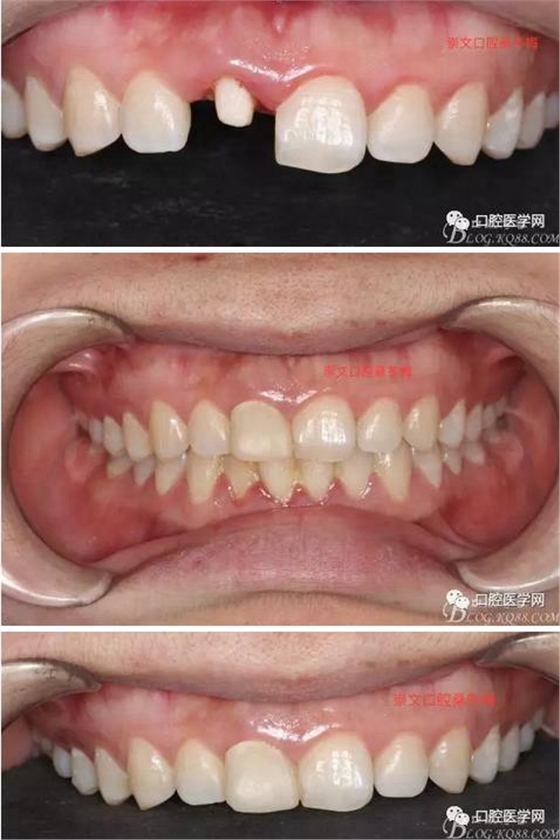

翻瓣 見(jiàn)11釉牙骨質(zhì)界存在,牙槽嵴頂?shù)接匝拦琴|(zhì)界不足2mm。21牙槽嵴頂?shù)接匝拦琴|(zhì)界不足2mm

去骨后,牙槽嵴頂?shù)接匝拦琴|(zhì)界達(dá)到2.5mm。保留11,21之間的牙槽嵴頂,不改變齦乳頭的狀態(tài)。

術(shù)后一周拆線